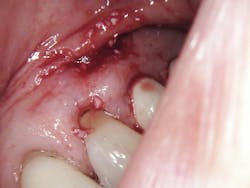

Aiming the laser at the affected area at a 45-degree angle, the first step was to remove the fibroma (figure 3). This was done easily after choosing the appropriate spot size, mist, and power. Following removal, the selections were adjusted for the next step, which was to make an incision in the gingiva. Keep in mind that it was vital to leave approximately 2 mm of keratinized tissue and raise the flap at this time. The laser’s precision allowed for the precise cutting that was needed.